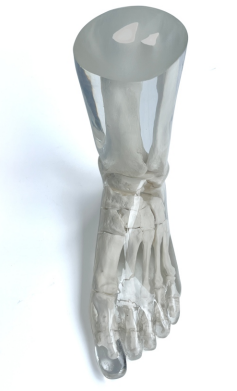

成人腿部模體,用于 X 射線 CT 和超聲波的成人腿部(肌肉)模型是一種基于人類(lèi)男性腿部平均解剖結(jié)構(gòu)設(shè)計(jì)的逼真模型。它具有所有基本的骨骼和

軟組織特征,使其成為學(xué)習(xí)、研究和測(cè)試醫(yī)學(xué)成像設(shè)備的理想工具。 模體可用于研究不同方向和定位技術(shù)的多種診斷性 X 射線 CT 和超聲程序。根據(jù)

要求,該產(chǎn)品可以根據(jù)不同的病理進(jìn)行定制,也可以用于特定的培訓(xùn)應(yīng)用。 模體尺寸:965.2 x 254 x 177.8 毫米,重量:12kg(約)